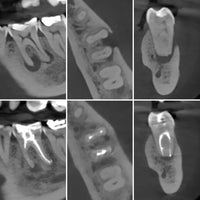

✅ Role of CBCT.